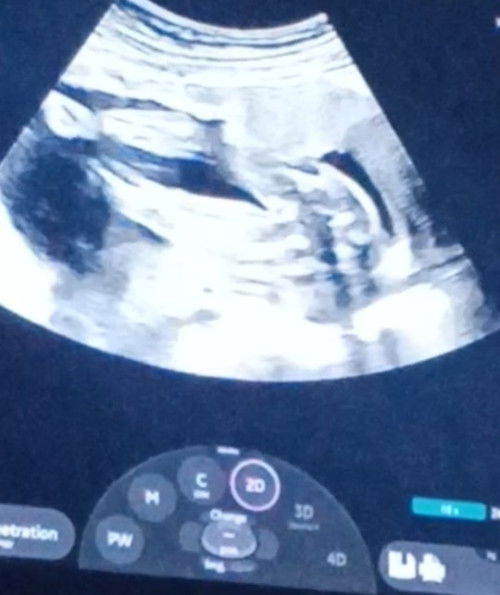

Gender. Girl or boy?

Sa tingin nyo po girl or boy? 19 weeks palang kasi yan dat time. D pa sure ung nag utz.thanks po #gender

GIRL